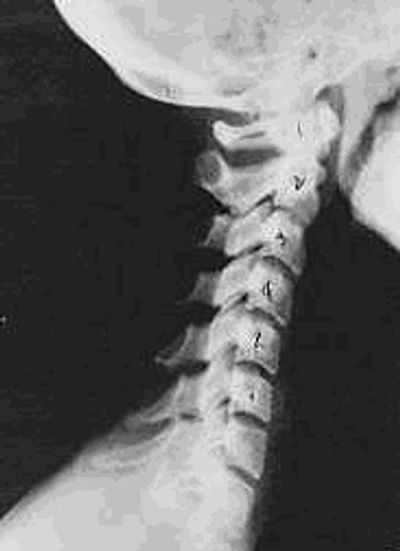

Near Normal

This is an x-ray view of the neck looking at the patient from the side. As with all the pictures on this page, the patient is looking to the right of the screen, so you are viewing the right side of their neck. This picture is a "near normal" spine. Compare this neck image closely with the ones you will see below. Notice the normal forward curve of the neck. This curve helps absorb shock similar to shock absorbers on your car. The white squares are called the vertebral bodies and should be clear and with well defined borders. The black spaces above and below the vertebral bodies are the discs. The discs should be thick and even. This type of arrangement is normal in the neck. Normal vertebrae in other parts of the spine also have similar characteristics to what is seen here.